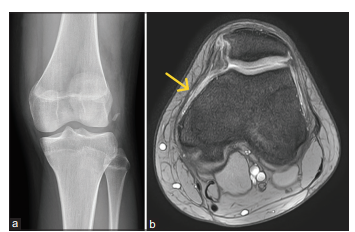

Bệnh nhân nữ, 20 tuổi, không có bệnh lý nền, bị chấn thương trong lúc nhảy – tiếp đất khi đang khiêu vũ, gây đau và biến dạng khớp gối trái, kèm theo mất chức năng vận động. Cô đến khám bác sĩ địa phương và được chẩn đoán bán trật bánh chè trái. Bệnh nhân được nắn chỉnh kín và mang nẹp bảo vệ gối [Hình 7]. Tuy nhiên, sau đó vẫn xuất hiện tình trạng trật bánh chè trái tái diễn từng lúc và đau gối kéo dài khi vận động. Bệnh nhân được chỉ định chụp cộng hưởng từ (MRI), cho thấy rách một phần dây chằng MPFL gối trái kèm theo dị vật rời trong khuyết gian lồi cầu [Hình 8]. Không phát hiện tổn thương dây chằng chéo hay sụn chêm đi kèm. Sau khi trao đổi, bệnh nhân đồng ý thực hiện phương pháp phẫu thuật xâm lấn tối thiểu như đã mô tả ở trên để điều trị tổn thương MPFL. Ca mổ diễn ra thuận lợi, và bệnh nhân được xuất viện sau 2 ngày mà không gặp biến chứng nào.